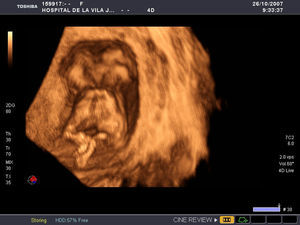

En la ecografía practicada por vía abdominal (fig. 1) se evidenció una gestación gemelar monocorial monoamniótica, en la que ambos fetos se encontraban unidos por el tórax y la parte superior del abdomen. Mostraban separación total de las cabezas, que estaban situadas cara a cara, y se visualizaban las columnas vertebrales y las cuatro extremidades en ambos fetos. Al estudiar la cavidad torácica compartida se identificó un corazón único, con latido cardíaco positivo. En el abdomen sólo fue visible un estómago en la gemela situada en el lado izquierdo y una vesícula biliar situada en la gemela derecha. Mediante Doppler color (fig. 2) se identificó la aorta en cada uno de los fetos y una única arteria renal en cada gemela. En una de las gemelas estaban presentes ambas arterias umbilicales, mientras que en la otra sólo era visible una de ellas. CRL=65,4mm. La translucencia nucal en una de las gemelas era de 5,6mm y en la otra de 5,8mm. Se practicó una ecografía 3D que confirmó el diagnóstico y fue muy ilustrativa para los padres. Informados acerca del mal pronóstico, los padres decidieron interrumpir la gestación. Tras la administración de prostaglandinas intravaginales, la paciente expulsó en bloque los dos fetos fusionados y la placenta. Posteriormente, se practicó un legrado ante la persistencia de restos y se administró gamma-globulina Anti-D, ya que la paciente era Rh negativa.

La ecografía 3D puede ser útil como complemento a la 2D. La técnica multiplanar permite la adquisición de un volumen en 8–9 s y su posterior análisis y almacenamiento10. Esta representación multiplanar permite asegurar o determinar de forma más clara el nivel y la extensión de las conexiones orgánicas. Además, las imágenes de superficie obtenidas mediante ecografía 3D y 4D son muy útiles para asesorar a los padres, dato que nuestra experiencia también confirma1,3,6,9.